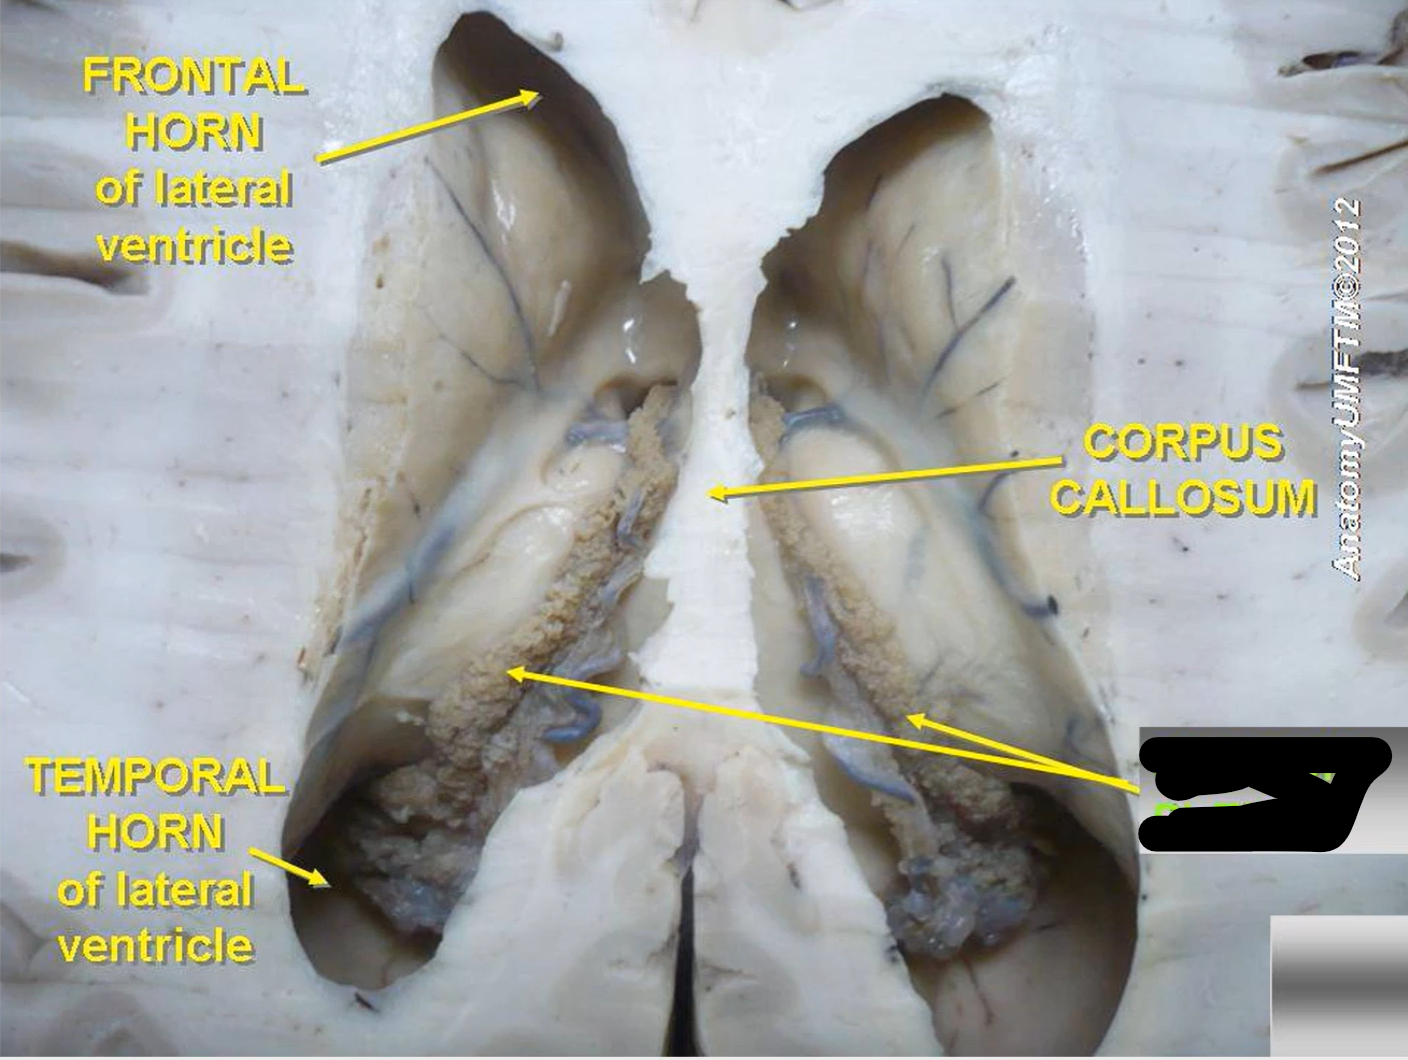

What do brain ventricles contain?

CSF

What makes CSF?

Choroid plexus

Where does CSF go from ventricles?

Subarachnoid space to enter circulation via arachnoid granulations

Choroid plexus

What carries CSF from 4th ventricle to subarachnoid space?

Median and lateral apertures

Arachnoid granulations

Lateral ventricles

Interventricular foramen

Third ventricle

Cerebral aqueduct

Fourth ventricle

Central canal